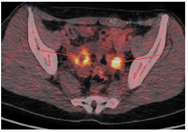

筛查卵巢,回顾病史发现,患者2017-06因偶有左下腹痛行妇科彩超示,左侧卵巢大小35 mm×24 mm;右侧卵巢大小33 mm×28 mm,其内可见31 mm×20 mm囊性无回声,内见分隔,内壁可见絮状低回声,子宫直肠陷窝可见液性暗区,范围43 mm×17 mm,未系统诊治。2017-12-18复查妇科彩超示,双侧卵巢内见囊性为主囊实不均光团回声,见少许血流,右侧卵巢大小为46 mm×34 mm,左侧为46 mm×29 mm。2017-12-20肿瘤标志物检查结果示,CA125为31.01 U/mL,CA153为10.82 U/mL,HE4为74 pmol/L。双侧卵巢肿物性质待查。PET/CT检查示,双侧附件区见囊实团块影,较大约4.4 cm×3.0 cm,伴边缘代谢增高(图3)。于2018-01-05在全麻下行经腹双侧卵巢肿瘤剥除术及卵巢重建术、盆腔粘连松解术、部分大网膜切除术。术后病理示,双侧卵巢病灶浸润性低级别浆液性癌,部分呈表面生长,局部伴微乳头特征,散在砂粒体,大网膜散在少量砂粒体,盆腔有种植(见图1)。免疫组化结果如图2所示,CK7(+),p53(+,<30%),PAX-8(+),ER(+),PR(+),WT-1(+),p16(部分+),Ki-67(+,30%)。腹水脱落细胞学检查找到可疑腺癌细胞。患者卵巢癌乳腺转移诊断明确,再次取右乳区段组织送病理未见残留癌。行遗传性乳腺癌/卵巢癌基因检测,结果为ATM、PALB2两个意义未明基因突变。